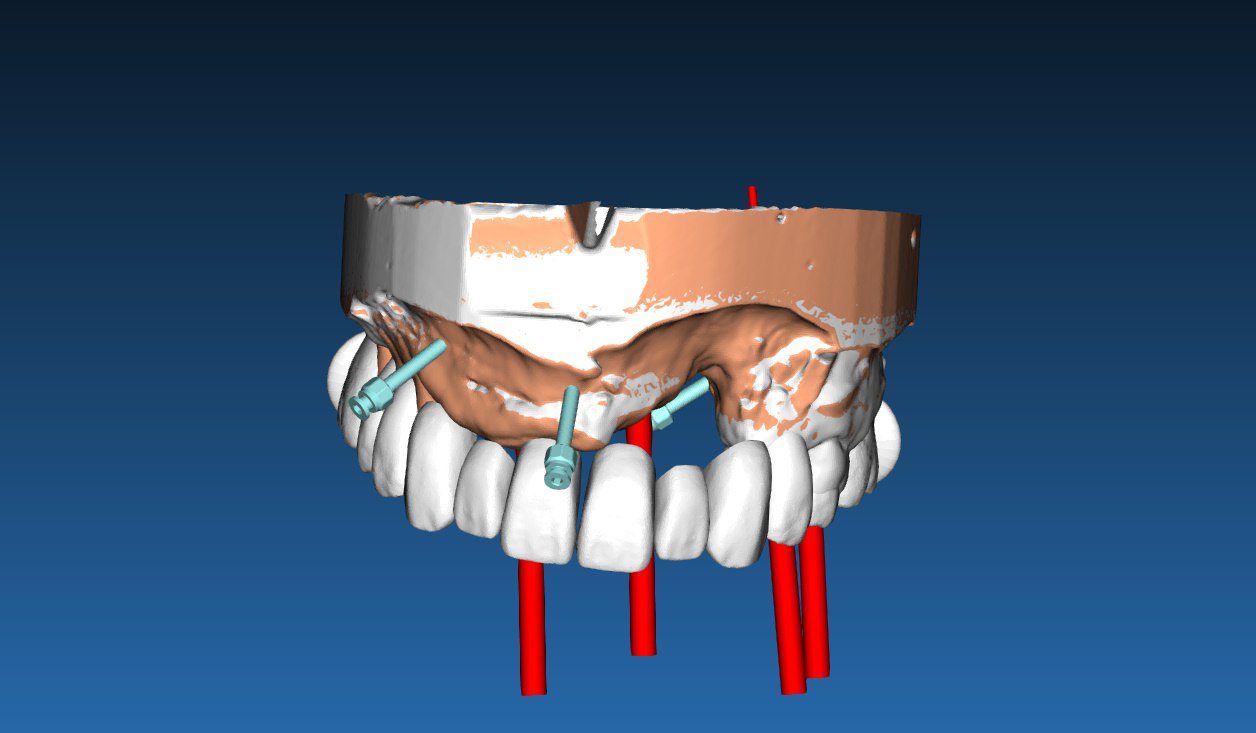

Навигационные системы используют высокотехнологичные программные и аппаратные решения, которые позволяют стоматологу «видеть» процесс имплантации в 3D-формате еще до начала операции. Это позволяет точно спланировать местоположение имплантов и минимизировать риск ошибок.

Навигационные системы используют высокотехнологичные программные и аппаратные решения, которые позволяют стоматологу «видеть» процесс имплантации в 3D-формате еще до начала операции. Это позволяет точно спланировать местоположение имплантов и минимизировать риск ошибок.

- Виртуальное моделирование челюсти: Все операции можно спланировать в цифровом виде, с учетом анатомических особенностей пациента.

- Создание индивидуальных шаблонов: Система разрабатывает шаблон для точной установки имплантов, который идеально подходит под конкретную анатомию пациента.

- Прецизионные шаблоны для имплантации: Эти шаблоны позволяют минимизировать человеческий фактор, обеспечивая высочайшую точность установки имплантов.